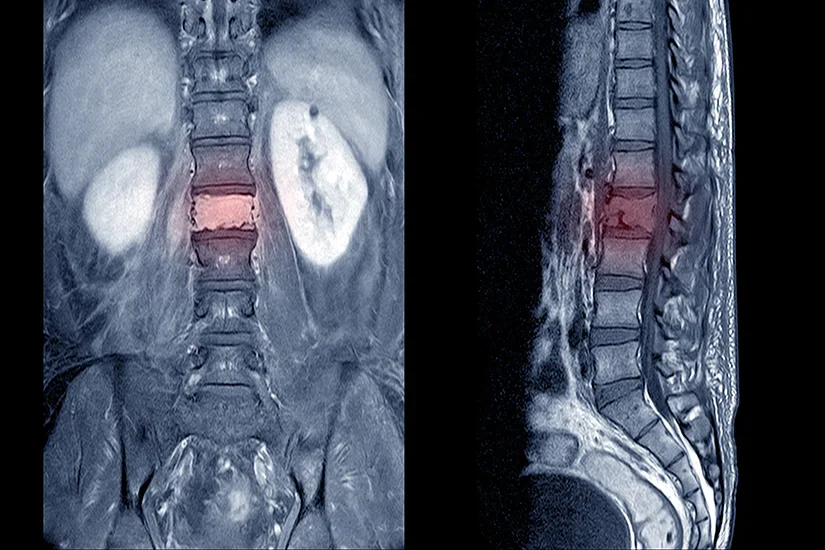

Tumorile medulare se clasifica in functie de localizarea lor in raport cu maduva spinarii: tumori intramedulare, localizate in interiorul maduvei spinarii, tumori extramedulare-intradurale, localizate langa maduva, insa delimitate de dura, foita care inveleste maduva spinarii si tumori extradurale, localizate in afara durei

Durerea de spate poate sa apara ca urmare a extinderii tumorii de la nivel medular la nivelul vertebrelor, cu erodarea osului si destabilizarea coloanei vertebrale. Cresterea tumorii la nivelul canalului rahidian si in interiorul maduvei spinarii produce compresiune medulara cu deficite neurologice importante si dureri care iradiaza pe traiectul radacinii nervoase afectate.

Cand tumora spinala comprima maduva spinarii se va indica tratamentul chirurgical. Interventia neurochirurgicala se efectueaza minim-invaziv sub microscop operator printr-o varietate de aborduri si are ca scop excizia tumorii in totalitate cu decompresiunea maduvei spinarii. Microscopul operator este esential pentru decomprimarea in siguranta a maduvei spinarii. Daca tumora a invadat si coloana vetebrala cu erodarea osului, pe langa decompresiunea maduvei se va realiza si stabilizarea coloanei utilizandu-se tehnici cu implanturi moderne.